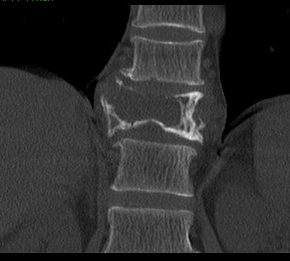

经过慎重考虑,老李决定返乡,并慕名来到我院就诊。脊柱外三科主任陈海龙看到老李的脊柱DR片后,顿感情况不妙,胸11椎体高度降低,椎体骨质及右侧附件结构严重破坏,幸运的是老李目前没有神经损伤症状,否则严重的话可造成双下肢截瘫。陈主任安排医师为老李紧急办理了住院手续,一边叮嘱他绝对卧床,一边加快各项相关检查。结合他的CT及MRI等影像资料显示,结果不过容乐观,不出所料,胸11肿瘤毫无疑问,而后穿刺活检的病理结果再次证实了医生的判断:骨巨细胞瘤。但幸运的是,经过全面彻底排查,未见肿瘤转移,那么此时此刻对老李来讲,完整彻底地切除肿瘤,是最优的选择。